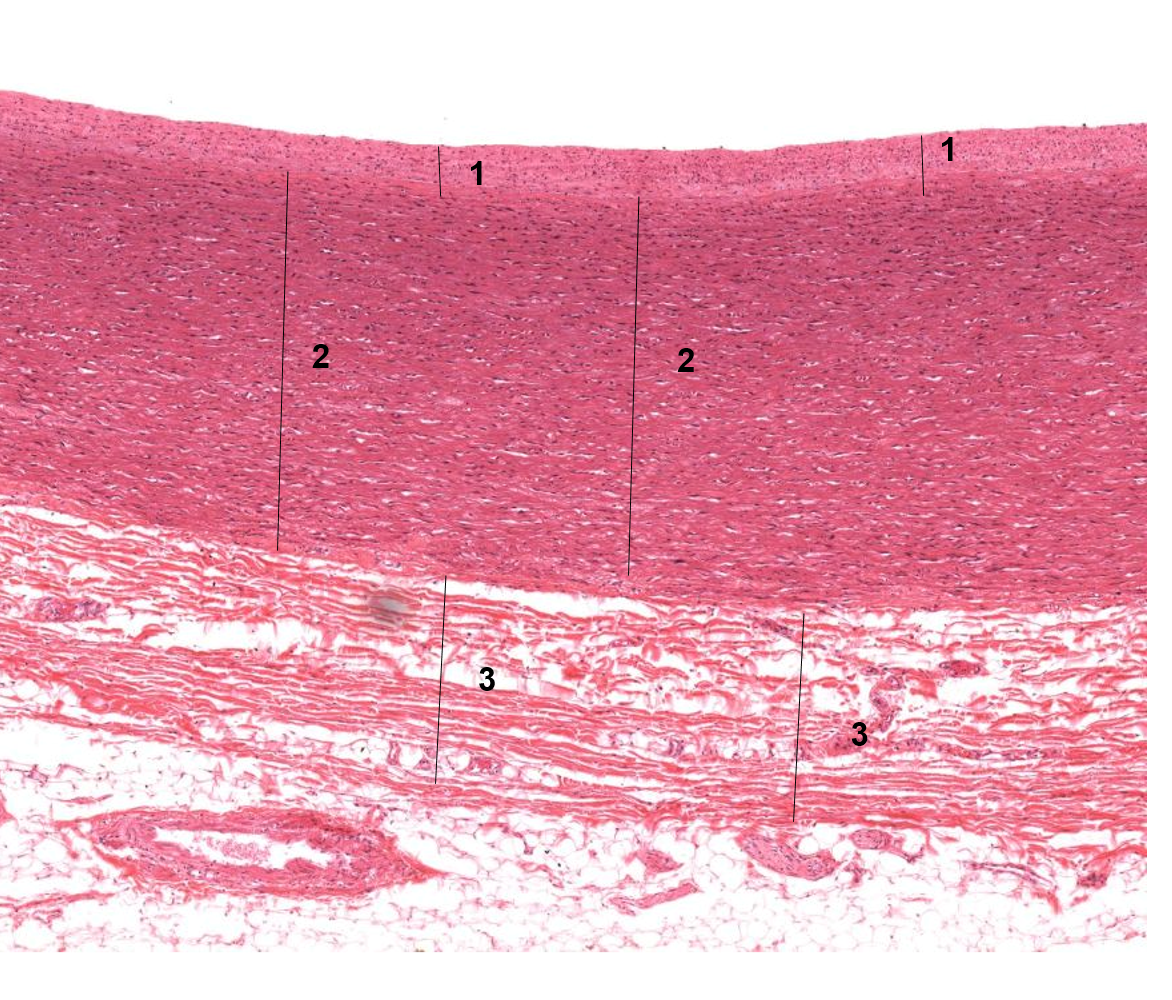

1: Epicárdio

2: Miocárdio

3: Artéria coronária